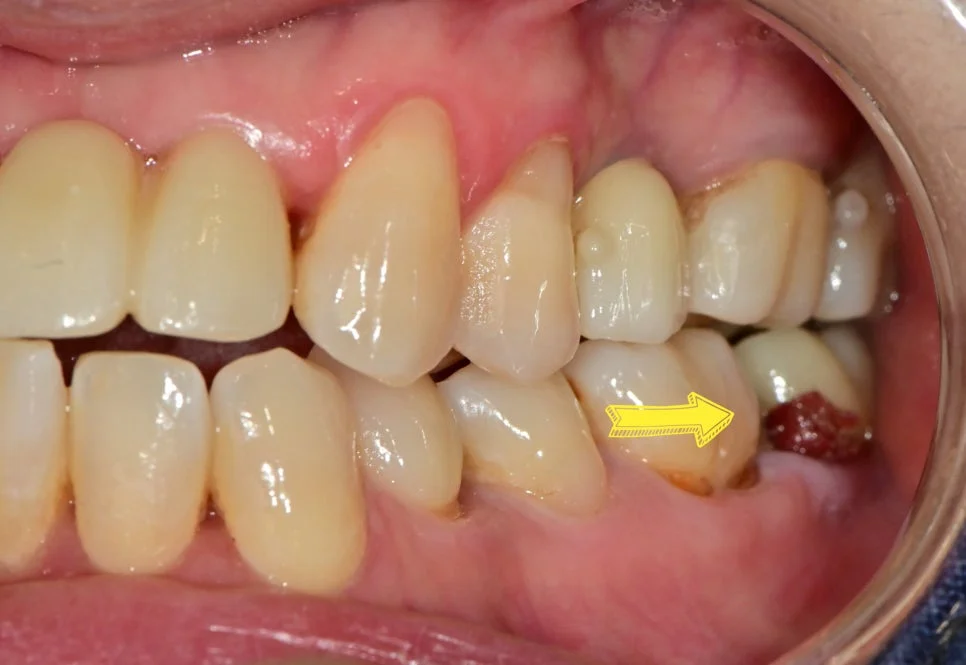

사례 2: 뿌리 충치 크라운 치료

왼쪽 아래 4번째 치아 뿌리 충치 사례입니다.

나이가 있으신 어르신들께 흔히 나타나는 문제인데요. 잇몸이 내려가면서 뿌리 부분이 노출되고, 뿌리의 상아질은 약하기 때문에 충치가 쉽게 생기고 빠르게 진행됩니다.

뿌리 충치 진단 임상 사진

뿌리 충치 진단 — 잇몸 하방까지 넓게 연장된 깊은 충치

아주 깊은 충치이지만 온도에 대한 반응이 없는 치아이기에 신경치료 없이 크라운 치료를 시행합니다.

이 뿌리 충치는 잇몸 하방까지 넓게 연장된 충치로 치료하기 상당히 까다로운데요.